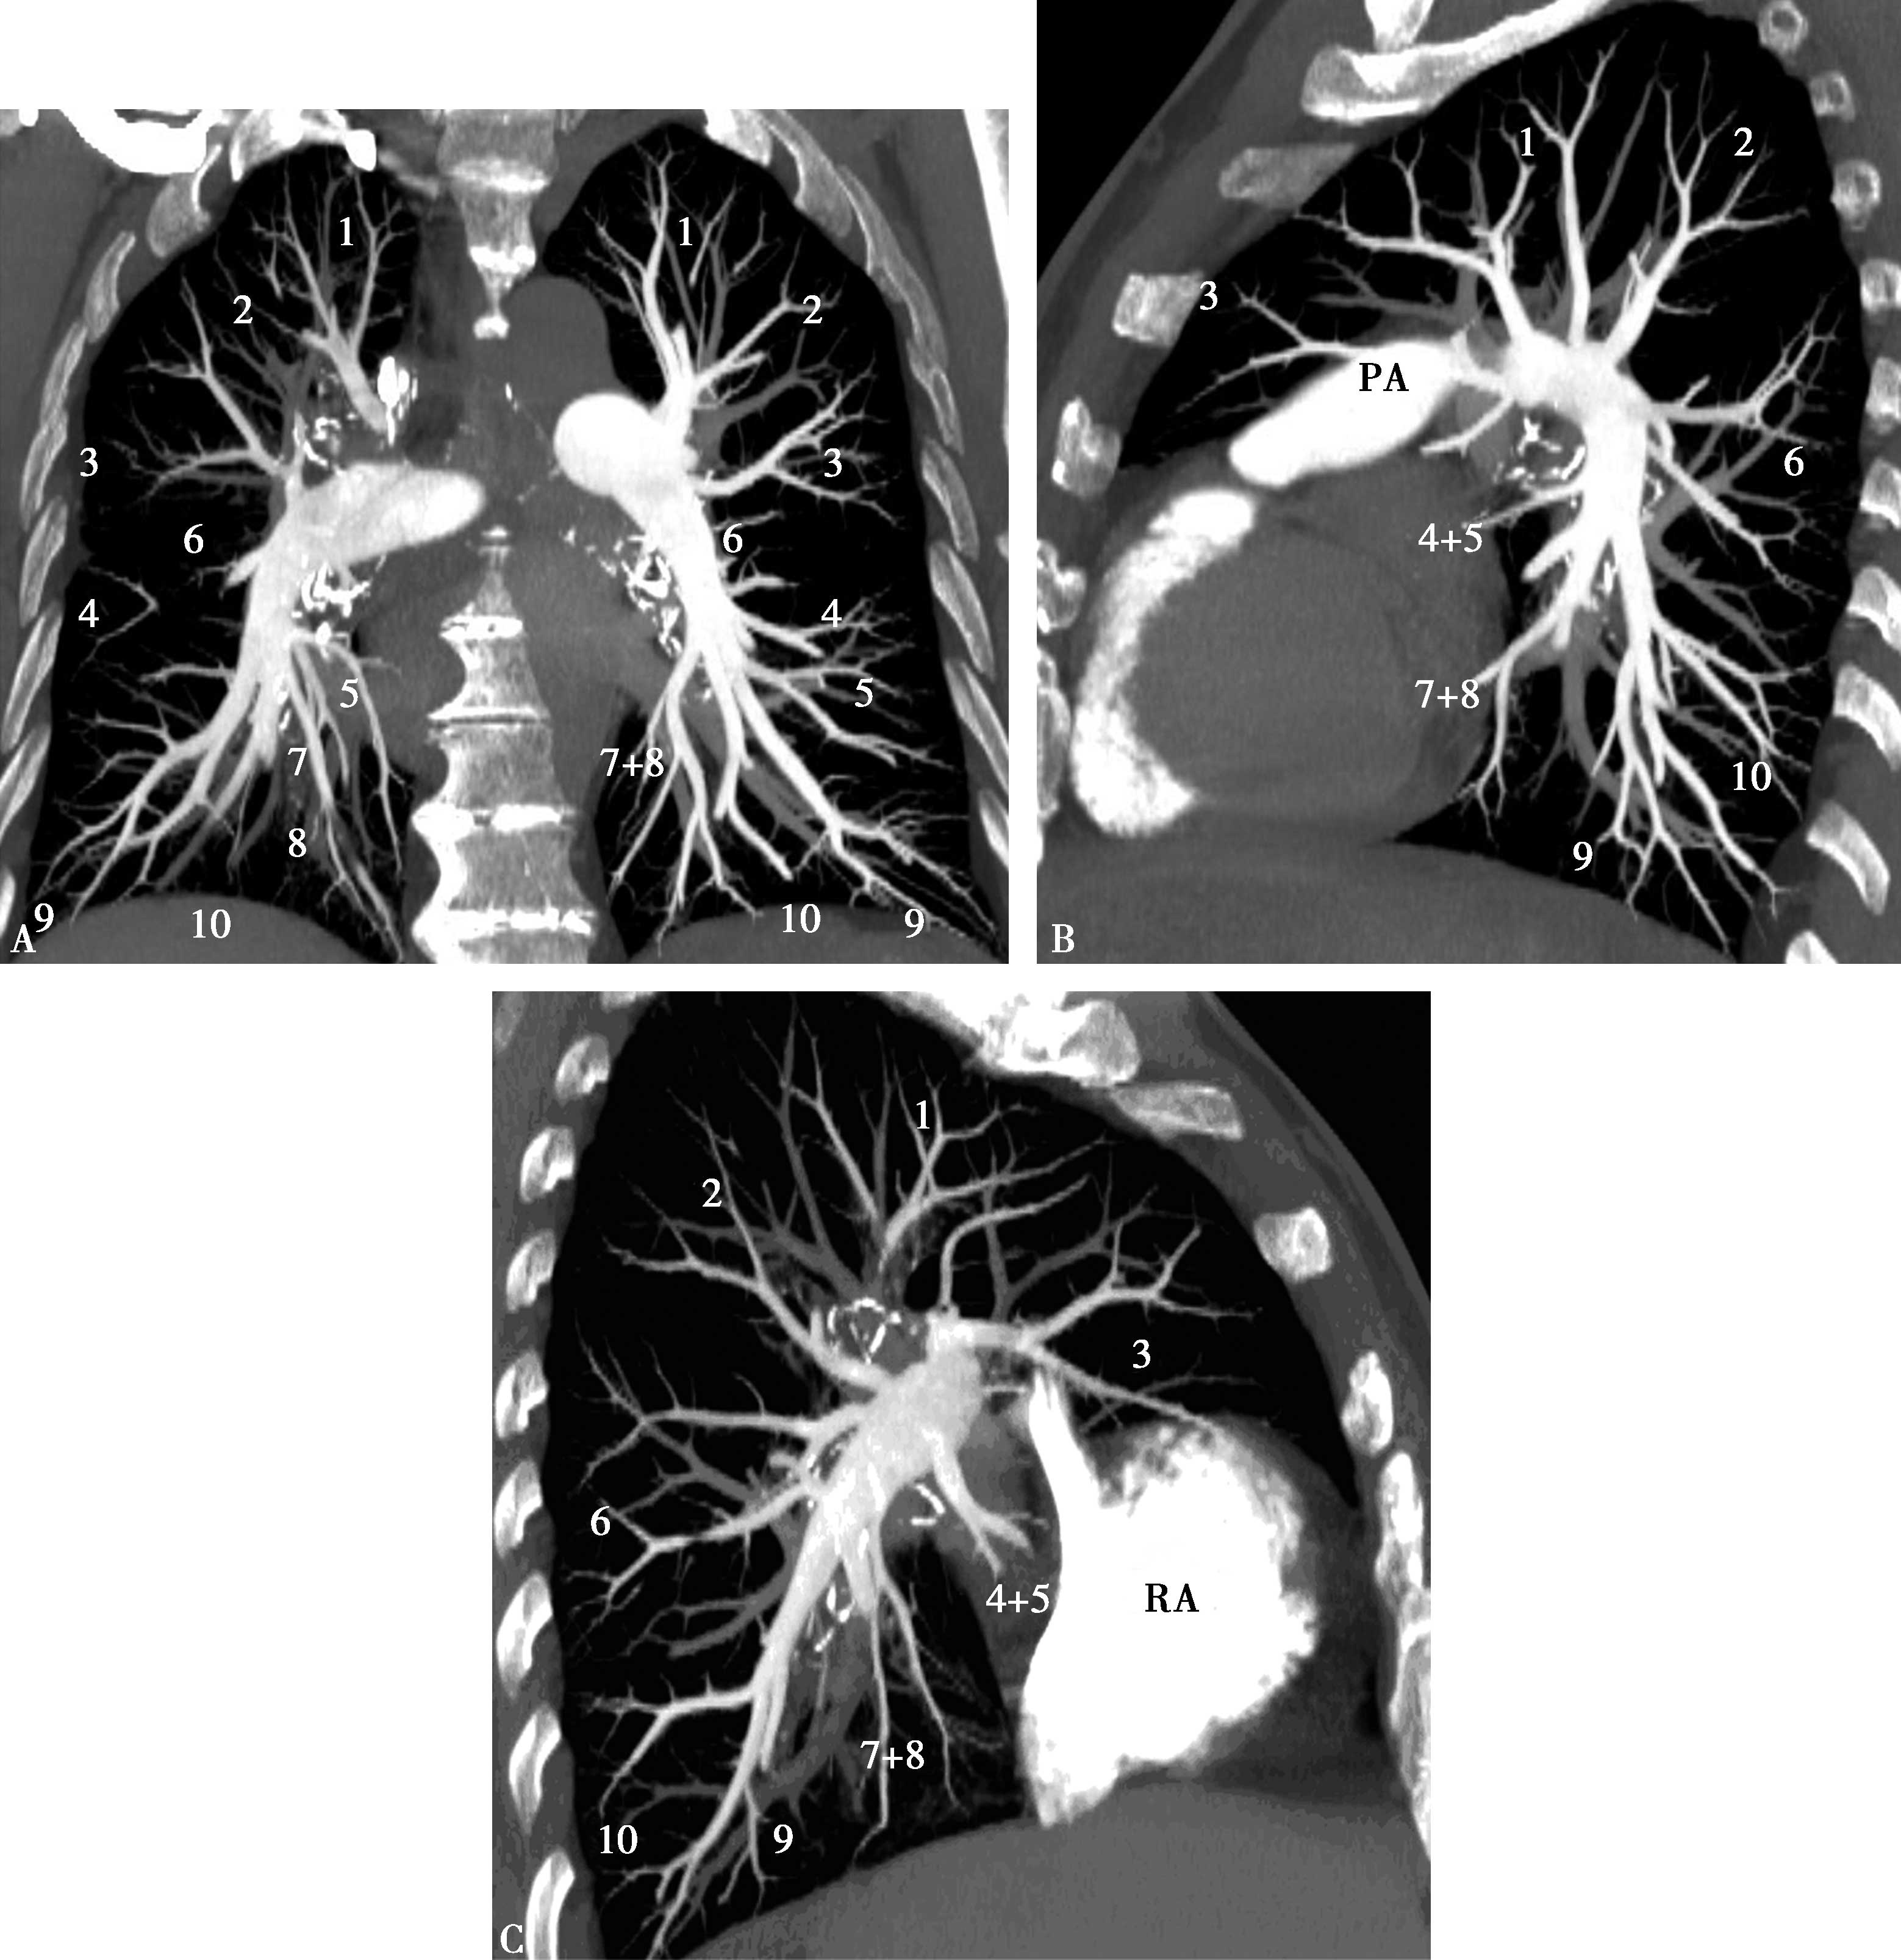

2.多层容积重组(MPVR,图8-2-8)

图8-2-8 肺动脉多层容积重建

上叶:1.尖段;2.后段;3.前段。(右肺)中叶:4.外侧段;5.内侧段。(左肺)舌叶:4.上舌段;5.下舌段。下叶:6.背段;7.内基底段;8.前基底段;9.外基底段;10.后基底段。PA:肺动脉;RA:右心房